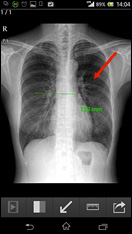

「HeSeL(ヘッセル)」は現在隣国韓国で大規模病院さまをはじめとし続々導入が進んでおります。この製品は個人情報流出の恐れのあるクラウドサービスではありません。重要な患者さまの情報流出の恐れがないので安心してご利用頂けます。